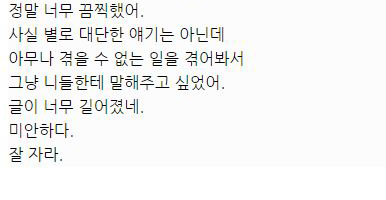

아래는 해당 글 작성자가 쓴 글.

대단한 얘기는 아니지만 중환자실에 3주동안 무의식으로 있었던 썰 풀어볼게